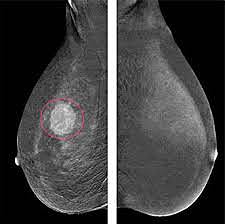

• Mammogram Screening

Mammogram Screening

Screening for breast cancer is done using a mammogram. It is recommended that women start screenings between 40-42. I plan to get my first mammogram at the age of 40 because I have a family history of breast cancer. Mammograms are an image of your breast taken with an x-ray machine. Your breast will be placed on a table and then compression will be applied in order to spread the tissue and view it fully. Ages 45-54 mammogram every year. 55 and older every two years.